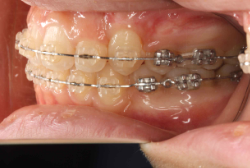

「歯並びの凸凹を直したい」という主訴で来院したケースです。診断の結果、たしかに「叢生」という隙間が足りないと言うことが原因の凸凹症例でした。

しかし、それ以上に問題なのは「前歯の噛み合い方が深すぎる」という症状で、初診の歯の正面写真を見ると下の前歯が全く見えません。こういう症状を矯正学では「過蓋咬合(かがいこうごう)」と言います。過蓋咬合を放置すると、将来的に顎関節に悪影響を与えるとされており、顎関節症の原因因子の一つです。また下の前歯の先端が、上の前歯の裏側の歯茎と強く接触するため、歯周病の原因にもなります。

検査の結果、凸凹が軽症なため非抜歯で矯正すること可能と判断、マルチブラケット装置にて治療しました。治療後は歯並びが綺麗になっただけでなく、噛み合わせ的にも正しい状態が確立しています。